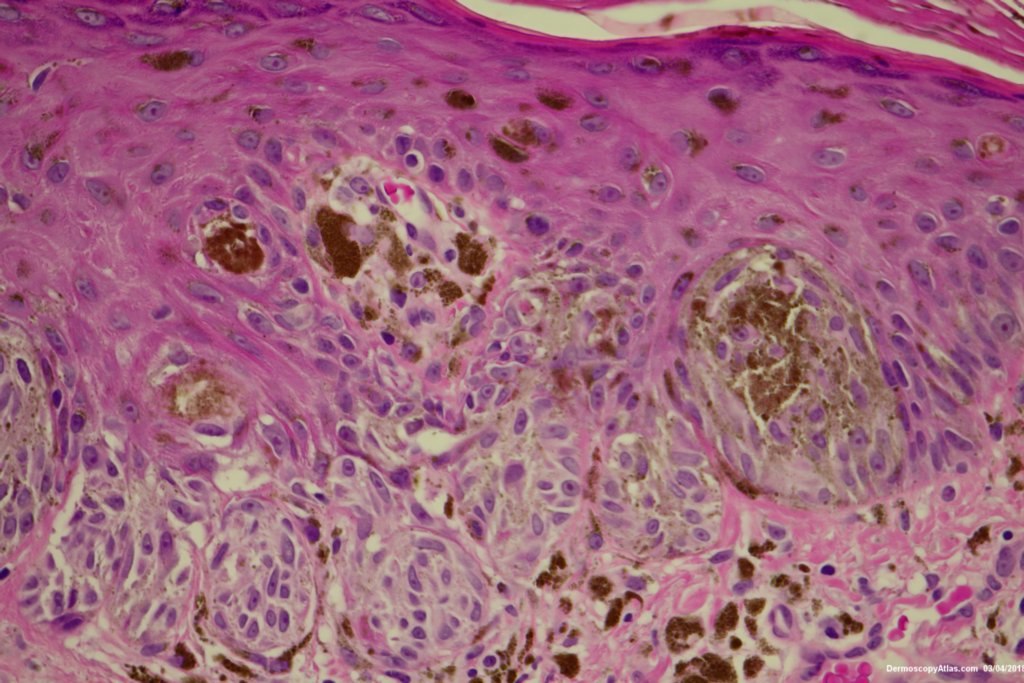

Image Number #3429 (Reed nevus)

Diagnosis: Reed nevus

Sudden onset of a new pigmented lesion on the shoulder. Dermatoscopy shows an actively proliferating lesion with peripheral pseudopods that involve most of the circumference. Clinically this was either a Reed nevus or a Spitzoid melanoma. The histology favours a Reed nevus.